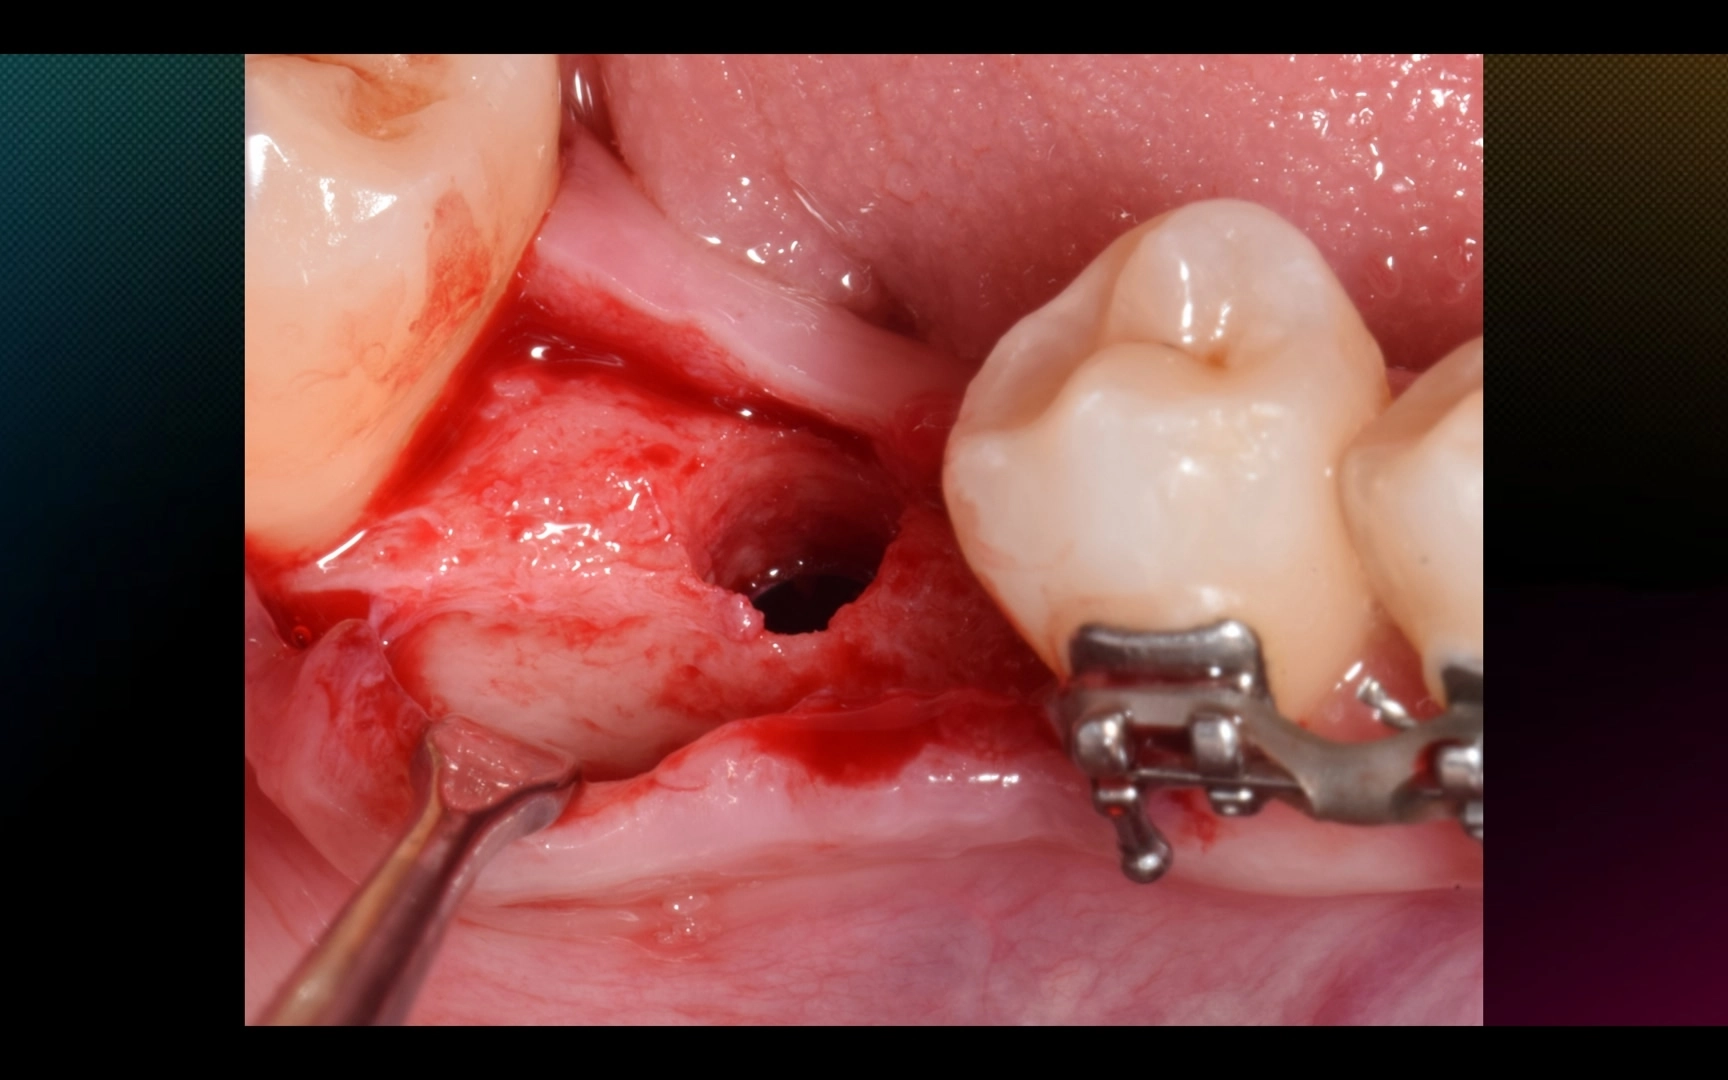

2. Через 5 месяцев после имплантации (пациентка раньше не смогла, обычно на н/ч выжидаем 3 месяца) — установка коронки с помощью ортопедического расщепления мягких тканей.